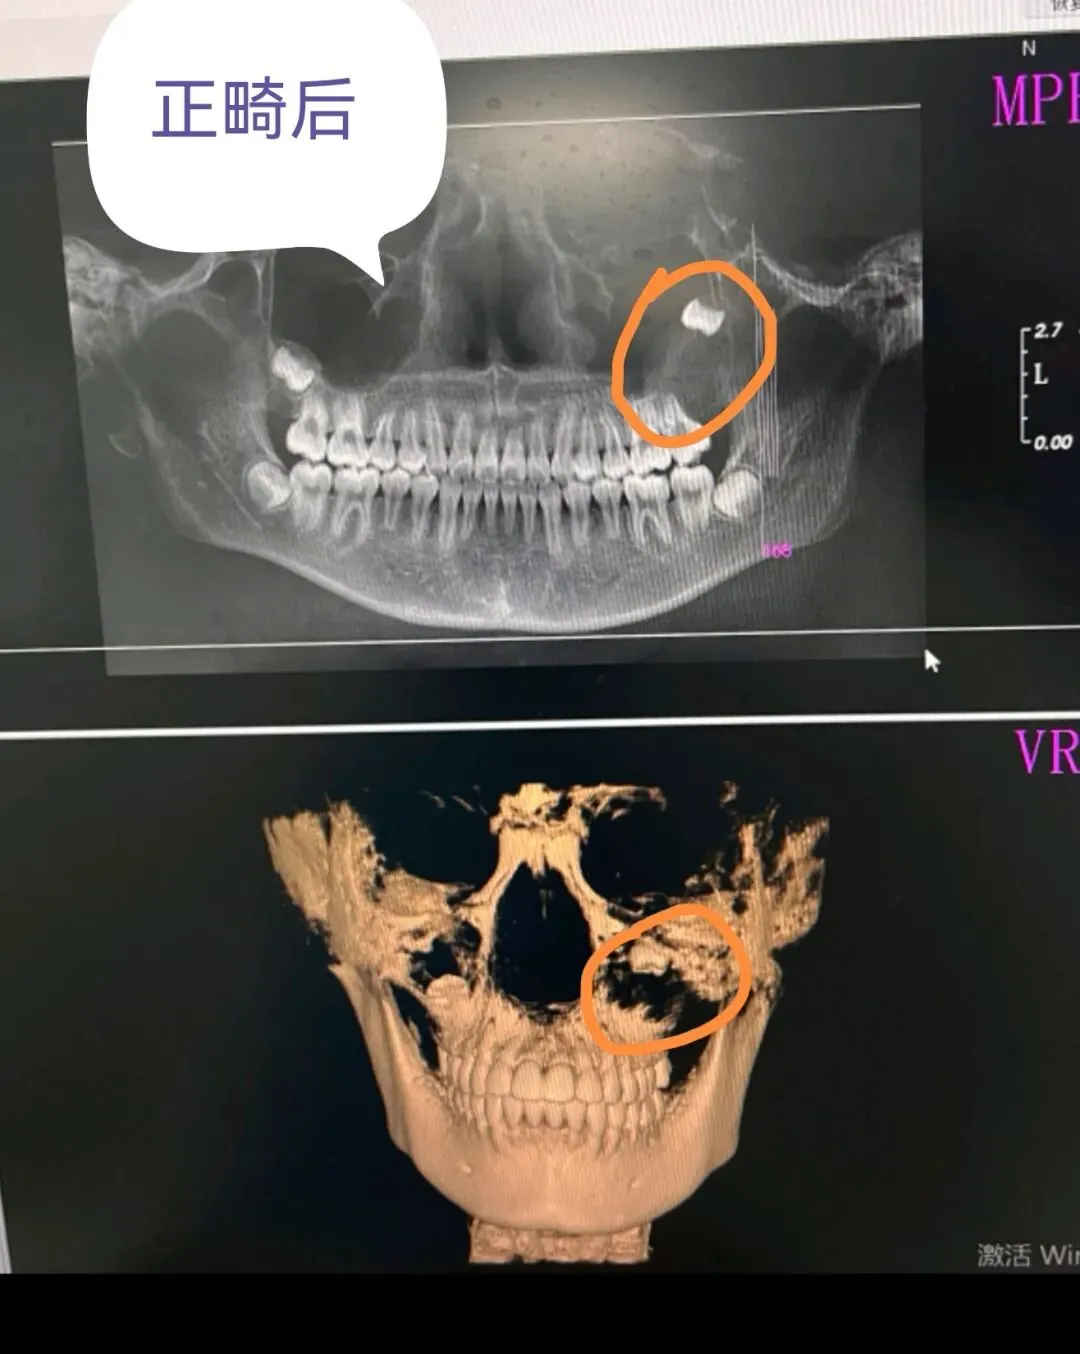

拆除矫治器时拍片,囊肿已经十分明显。

却因为医院未提供规范的影像分析报告,再加上正畸医生的专业能力与责任心双重缺失,最终导致漏诊,延误了治疗。

最后因囊肿太大,孩子不得不接受两次全麻手术。